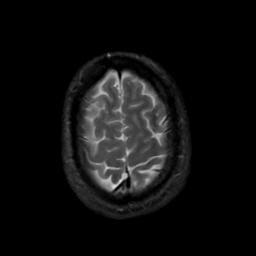

MR Study #12, May 12, 1991 -- Slice #43

[Home][Help][Clinical][Tour 1][Tour 2] Slice 43